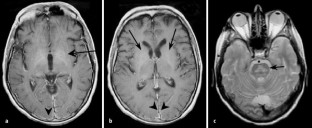

Abb. 1a–c.